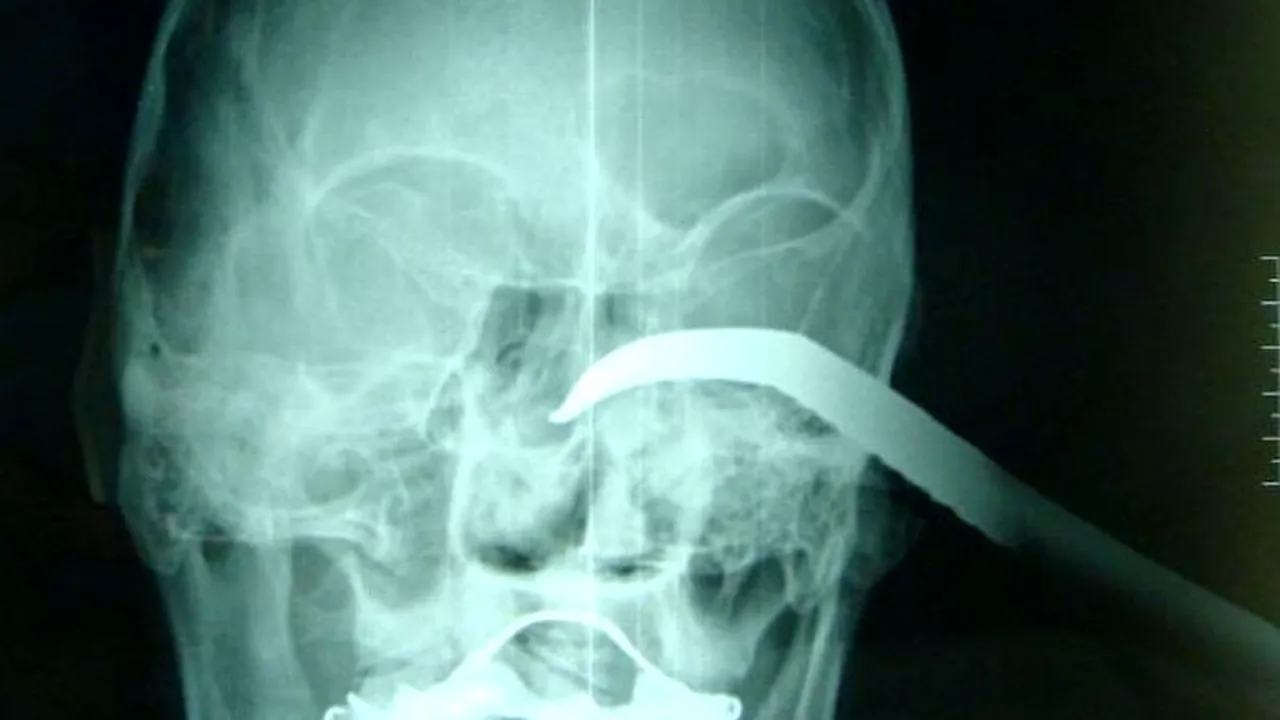

Medicii i-au făcut o radiografie lui Wang Chengge și au constat că rana făcută de cârlig avea 5 centimetri adâncime, dar au rămas surprinși când au constat că globul ocular al acestuia era intact. Bărbatul a fost operat și își va recăpăta total vederea.